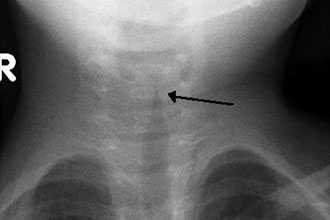

- Так же при проведении операции трахеотомии, когда в первые кольца трахеи ставится трахеотомическая трубка, голос так же отсутсвует полностью..

- Жизнеугрожающая обструкция верхних дыхательных путей, требующая неотложного врачебного вмешательства в дыхательные пути, такого как трахеотомия или интубация.

Хирургическое лечение не рекомендовано при неосложнённом течении ларингита. Проведение экстренных хирургических вмешательств необходимо при осложнённых формах и жизнеугрожающих состояниях, например при крайне выраженном стенозе гортани, эпиглоттите и абцессе. Проводят трахеостомию или инструментальную коникотомию [27] .